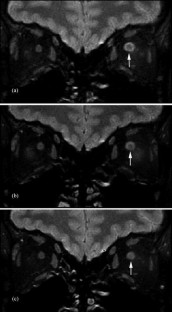

Optic nerve sheath dilatation or gadolinium-enhancement on magnetic resonance imaging in acute optic neuritis have been previously reported but have been thought to be rare occurrences. This study recruited 33 patients with acute unilateral optic neuritis. All had their optic nerves imaged with fat-saturated fast spin-echo (FSE) imaging, and 28 had imaging before and after triple-dose gadolinium-enhanced fat-saturated T1-weighted imaging. Follow-up imaging was performed on 20 patients (15 following gadolinium). A dilated subarachnoid space at the anterior end of the symptomatic optic nerve on FSE imaging was seen in 15/33 cases. In three of these cases, dilatation was visible on short-term follow-up. Optic nerve sheath enhancement was seen in 21/28 cases acutely: seven at the anterior end of the lesion only, five at the posterior end only and nine at both ends. Optic sheath enhancement was seen in 13 patients on follow-up. This study suggests that optic nerve sheath dilatation on FSE images and optic nerve sheath enhancement on triple-dose gadolinium-enhanced images are common findings in acute optic neuritis. Optic nerve sheath dilatation may be due to inflammation of the optic nerve, with its associated swelling, interrupting the communication between the subarachnoid space of the diseased optic nerve and the chiasmal cistern. Optic nerve sheath enhancement suggests that meningeal inflammation occurs in optic neuritis, in agreement with pathological studies of both optic neuritis and multiple sclerosis.